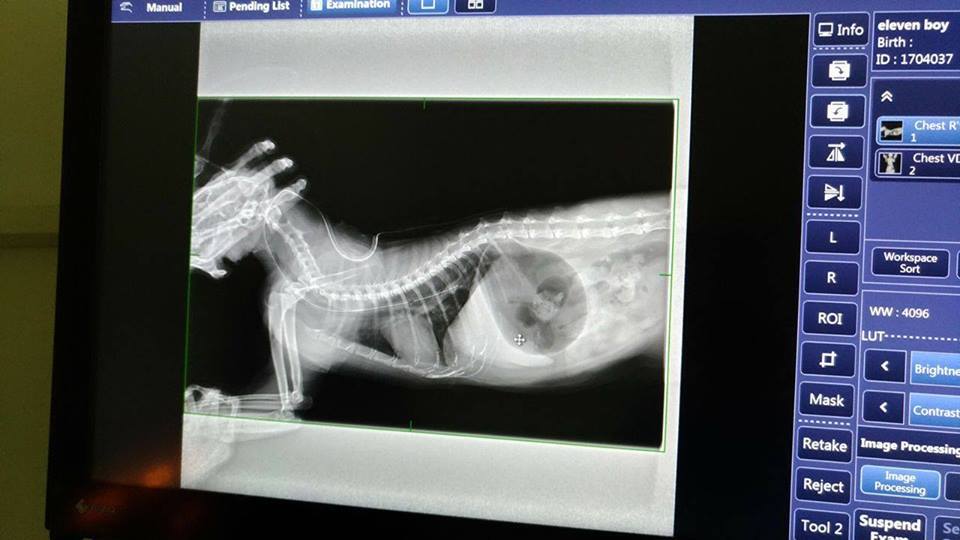

11郎今日有做胃部超音波,

但胃部空氣太多無法看到食物的狀況

且在灌食管中看到一大截的空氣

請照護人員在灌食且更換針筒時

記得將管子反摺以免空氣進入

另因11郎呼吸聲有點大

所以也有照x光確認肺部並無異狀